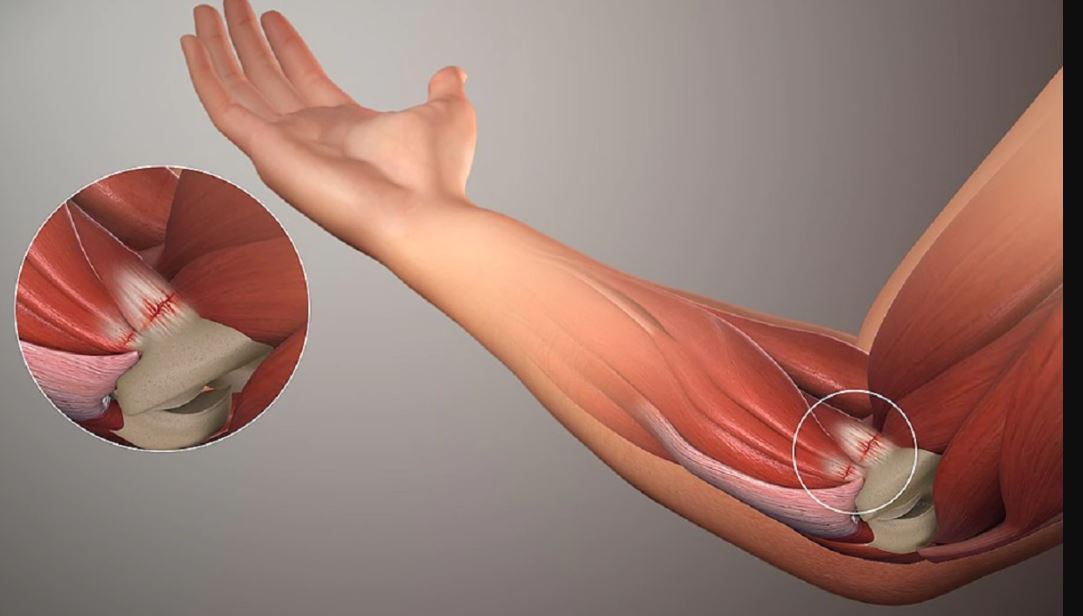

मांसपेशिहरु र जोड्ने मा प्रभाव – उमेर बढ्दै गएपछि सबैभन्दा धेरै असर मांसपेशिमा पर्छ । शारीरिक शक्ति कमजोर हुन थाल्छ। यसलाई राम्रो बनाउनको लागि स्ट्रेन्थ ट्रेनिन्ग लिन जरुरी छ। यसले मांसपेशीको घनत्व बढाउछ र सन्तुलन पनि सहि हुनेछ। यस उमेरमा जोर्नी दुखाई र आर्थराइटिस पनि हुन्छ। शरीरमा पानी कमी हुन दिनुहुदैन। पानीको अभावले टिश्युलाई पनि असर गर्छ।